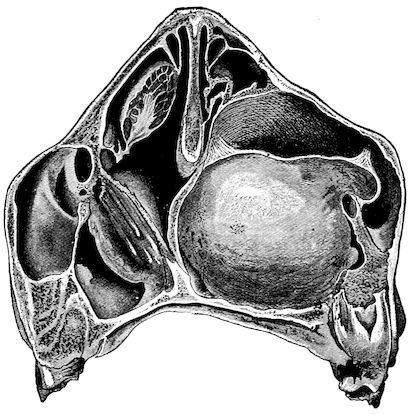

Fig. 1.—Rachitis in a young goat.

Fig. 1.—Rachitis in a young goat.